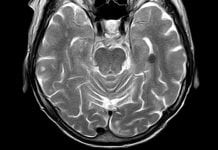

Neurodegenerative diseases are those conditions which primarily affect the neurons in the human brain. Neurons are the building blocks of the nervous system which normally don’t reproduce or replace themselves. Damage or disease can lead to such neurodegenerative diseases as Parkinson’s, Alzheimer’s, and Huntington’s disease.